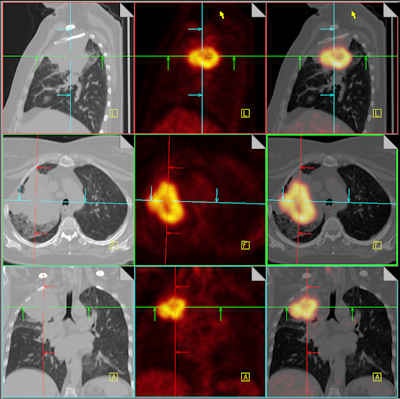

| Combining CT with PET adds value for staging non-small cell lung cancer and for monitoring the effectiveness of that treatment. These fused PET/CT images differentiate a large right upper lobe cancer from surrounding atelectasis. Image courtesy of Dr. Nigel Howarth, Institute of Radiology, Clinique des Grangettes, Geneva, Switzerland. Previously published in ECR Today, 5 March 2011. |